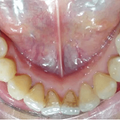

一個(gè)小伙對(duì)口腔醫(yī)師說(shuō)“醫(yī)師,我才22歲兩顆大牙就爛了,該怎么辦?如果不能夠徹底的解決這個(gè)問(wèn)題的話,那么我后面幾十年是不是只能吃一些比較軟的東西了?據(jù)統(tǒng)計(jì)國(guó)內(nèi)成人和老人牙齒病患病率是百分之88.1到百分之98.4,近些年來(lái)蛀牙,爛牙,牙周炎等各種危害牙齒健...

我從小就比較喜歡喝果汁,橘子汁、芒果汁、橙汁、椰汁、柚子汁……各種果汁輪流喝不停,雖然說(shuō)喝果汁給我?guī)?lái)了很大的驚喜,比如皮膚非常好,但是又遇到一個(gè)很大的問(wèn)題,就是,牙齒,都快變得跟橘子一個(gè)顏色了,什么大牌口紅涂上去,都被我涂成了山寨的感覺(jué)...